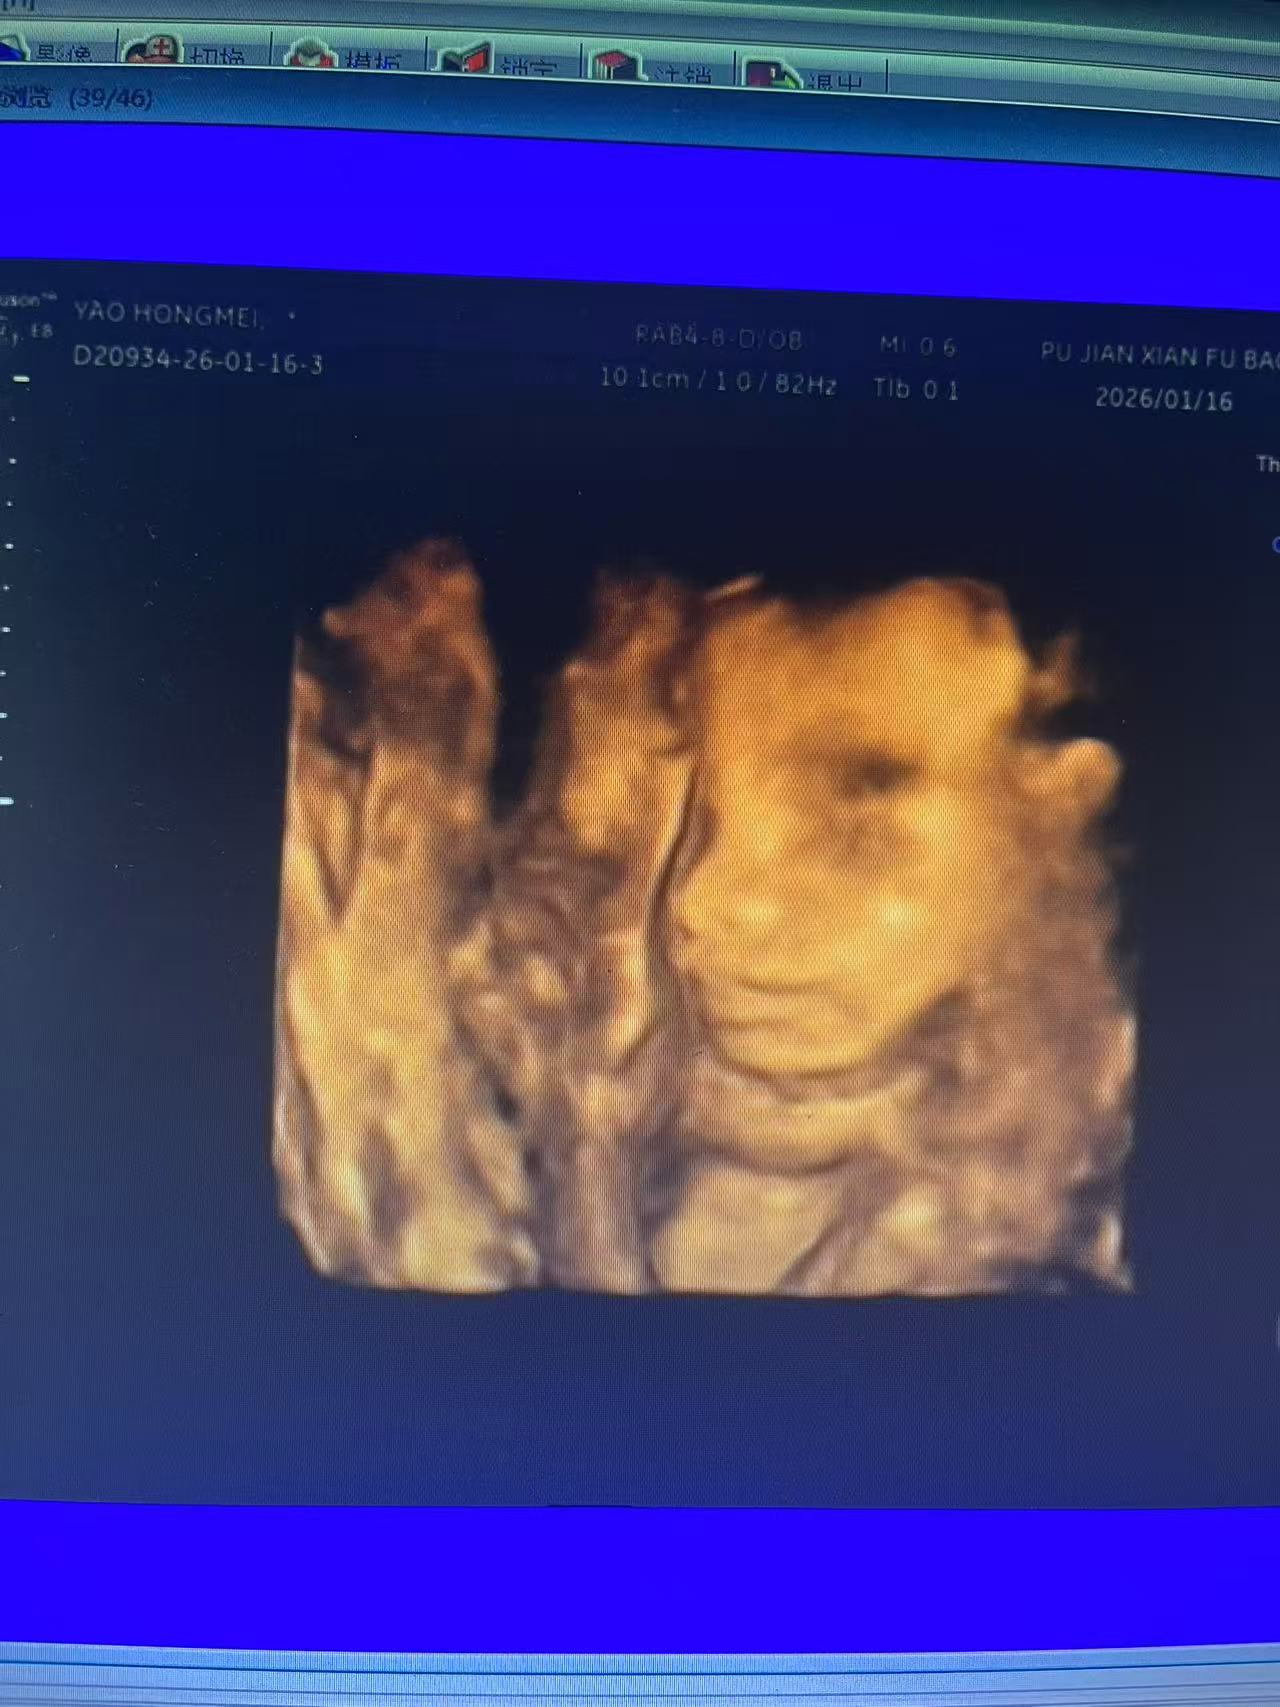

今天去医院做四维检查,结果被赶出来两次,宝宝一直趴着不动,最后发现左侧肋骨有点欠佳,医生建议去更权威的医院复查。虽然说不影响宝宝健康,但还是有点担心。姐妹们有没有遇到过类似情况啊?

做四维前记得吃点巧克力让宝宝活跃起来,我就是忘了吃才这么折腾。不过最后还是看到了宝宝的小脸,虽然医生说肚皮太厚看得不太清楚[捂脸]